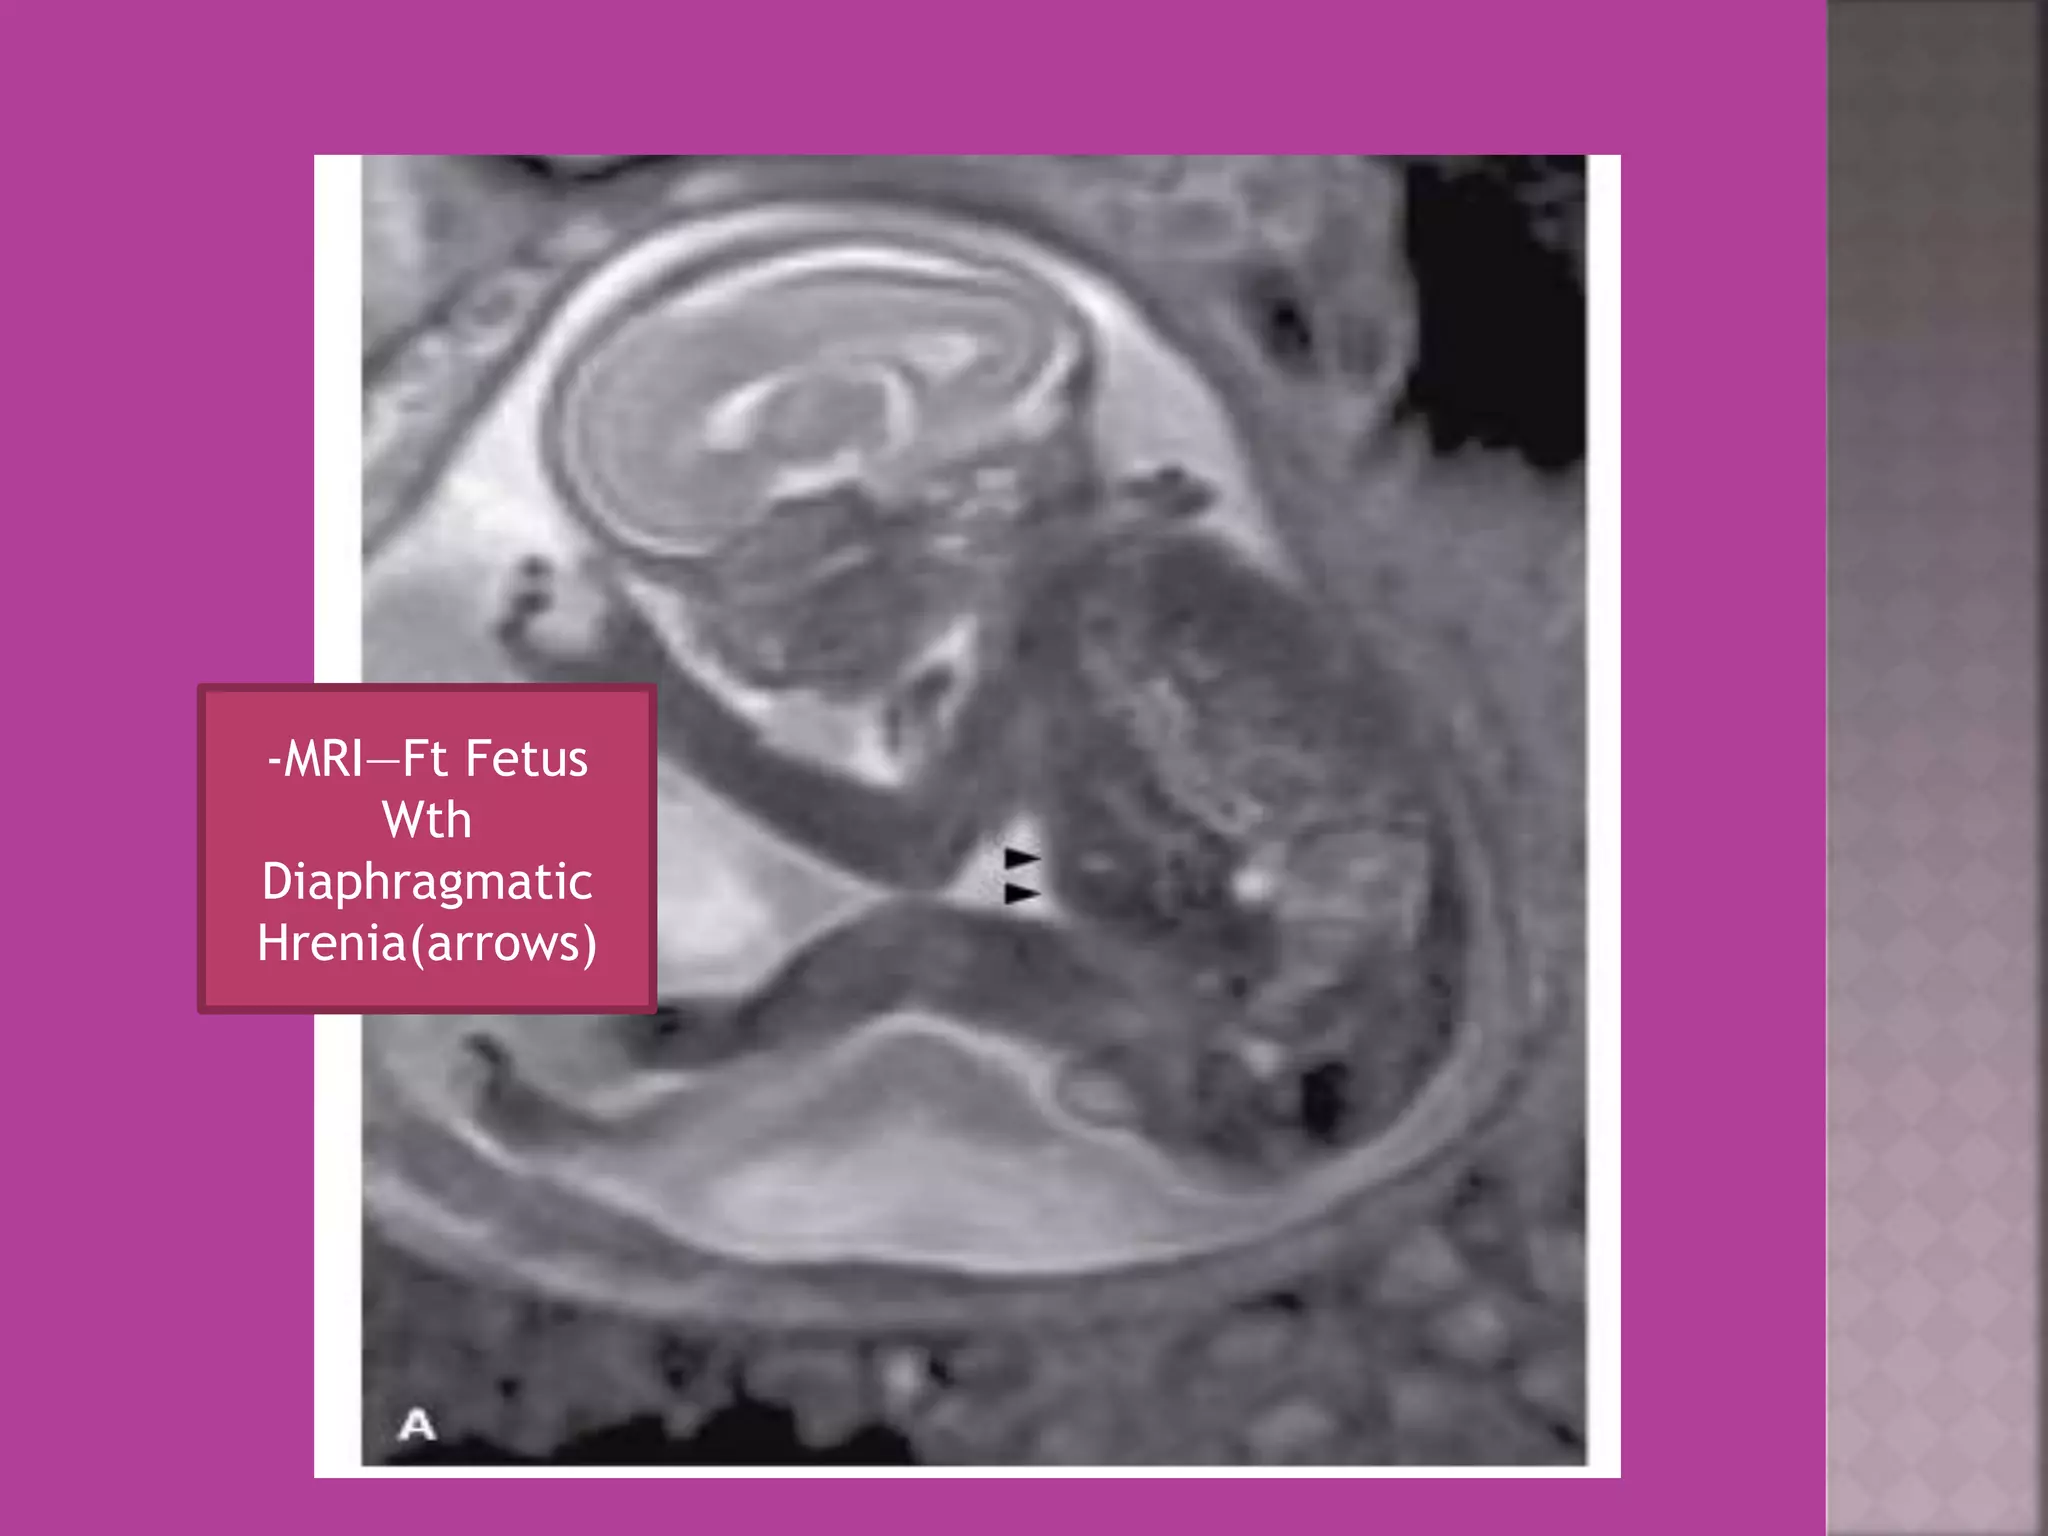

-MRI—Ft Fetus

Wth

Diaphragmatic

Hrenia(arrows)

 As it is safe in pregnancy –it is useful in diagnosis of

obstetrical conditions as well s differentiation of

tumors (benign / malignant ) complicating pregnancy.